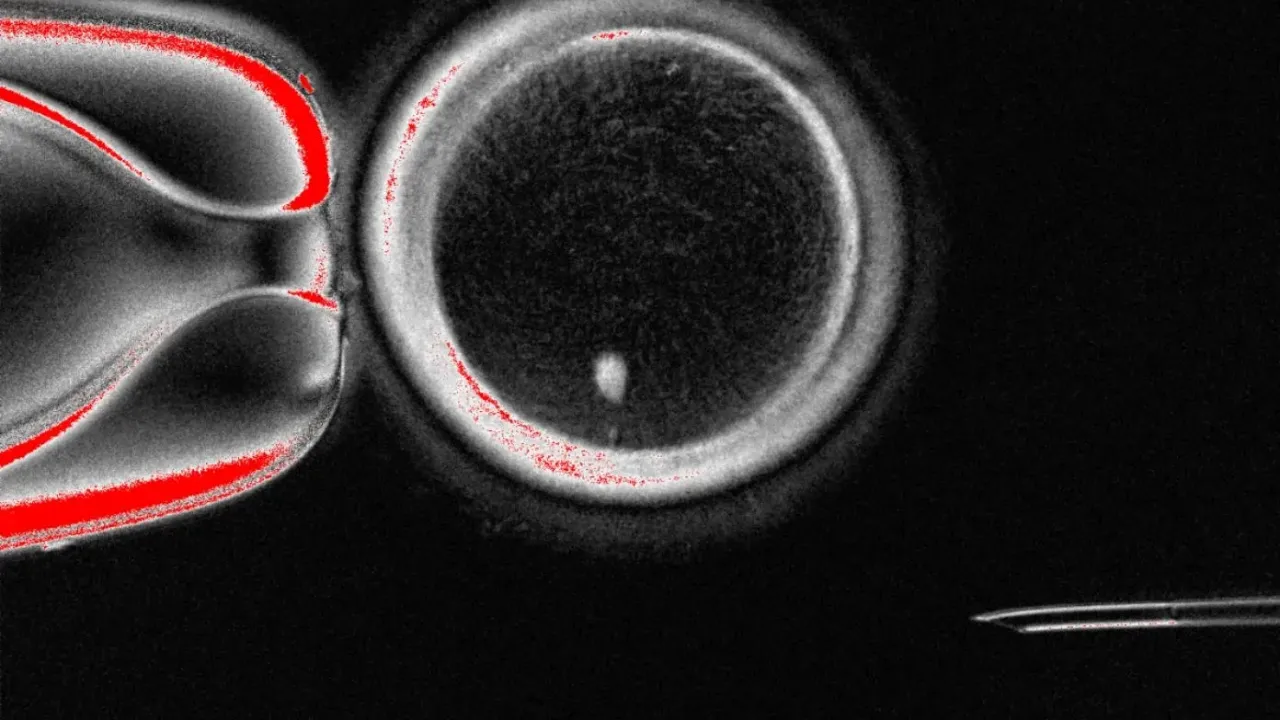

Salı günü Nature Communications dergisinde yayınlanan kavram kanıtlama çalışması, hücrenin genetik bilgisinin çoğunu içeren kısmı olan çekirdeğin sıradan bir insan deri hücresinden alınıp, çekirdeği çıkarılmış bir donör yumurtasına nakledilmesini içeriyordu. Araştırmacılar, 82 adet işlevsel insan oositi veya olgunlaşmamış yumurta hücresi üretti ve bunlar daha sonra laboratuvarda döllendi.

Çoğunlukla Portland'daki Oregon Sağlık ve Bilim Üniversitesi'nde bulunan ekip, doğal hücre bölünmesini taklit ederek, 23 kromozomdan oluşan bir setin atılmasını ve geriye işlevsel bir yumurta hücresinin kalmasını sağlayan bir yöntem geliştirdi. Araştırmacılar bu işleme "mitomeyoz" adını verdi.

Ancak, çalışma sırasında üretilen yumurtaların %9'undan azı embriyo gelişiminin blastosist aşamasına, yani döllenmeden sonraki beş veya altı güne ulaşabilmiştir. Bu, embriyoların genellikle tüp bebek tedavisi sırasında rahme transfer edildiği zamandır.

Amato ayrıca, ortaya çıkan tüm embriyoların kromozomal olarak anormal olduğunu, bunun ya toplam kromozom sayısının yanlış olması ya da her çiftten bir tane bile olmaması nedeniyle olduğunu açıkladı. Embriyoların sağlıklı bebeklere dönüşmesinin beklenmeyeceğini ve muhtemelen hepsinin erken gelişmeyi durduracağını da sözlerine ekledi.